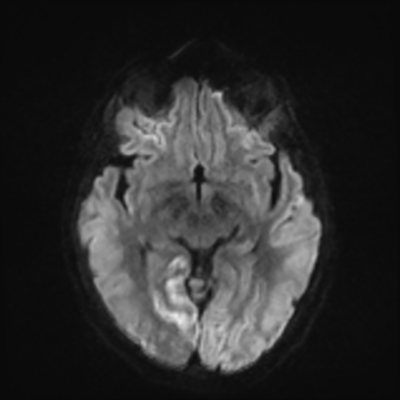

MRI brain (DWI)

MRI brain (DWI) 2/24 2/24

You can clearly see diffuse cortical and basal ganglia diffusion restriction, and that of his deep cerebellar nuclei as well. The right occipital lobe abnormalities are a little more prominent, but then you remember that he is known to have had a right occipital stroke weeks ago.

In reviewing his data, you know that he doesn't have any of the strong predictors of a poor neurologic prognosis. However, based on these findings on MRI, along with the absent reactivity on cEEG, you are able to tell the primary team and the patient's family that he is likely to have a poor prognosis, based on these multiple moderate predictors. Recovery is not completely impossible-- there is more uncertainty with this prognostication than if we were able to get SSEPs-- but you're very worried about his outlook and that any potential recovery would require a very protracted rehabilitation period. Given his high cervical cord injury level, tracheostomy would be required anyway. So, it comes down to whether his family thinks he'd want to pursue these aggressive measures.